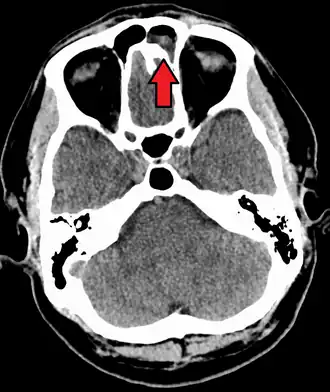

For sinusitis lasting more than 12 weeks, a CT scan is recommended.[66] On a CT scan, acute sinus secretions have a radiodensity of 10 to 25 Hounsfield units (HU). In a more chronic state, they become more viscous, with a radiodensity of 30 to 60 HU.[69]

-

MRI image showing sinusitis. Edema and mucosal thickening appear in both maxillary sinuses. -

Maxillary sinusitis caused by a dental infection associated with periorbital cellulitis -